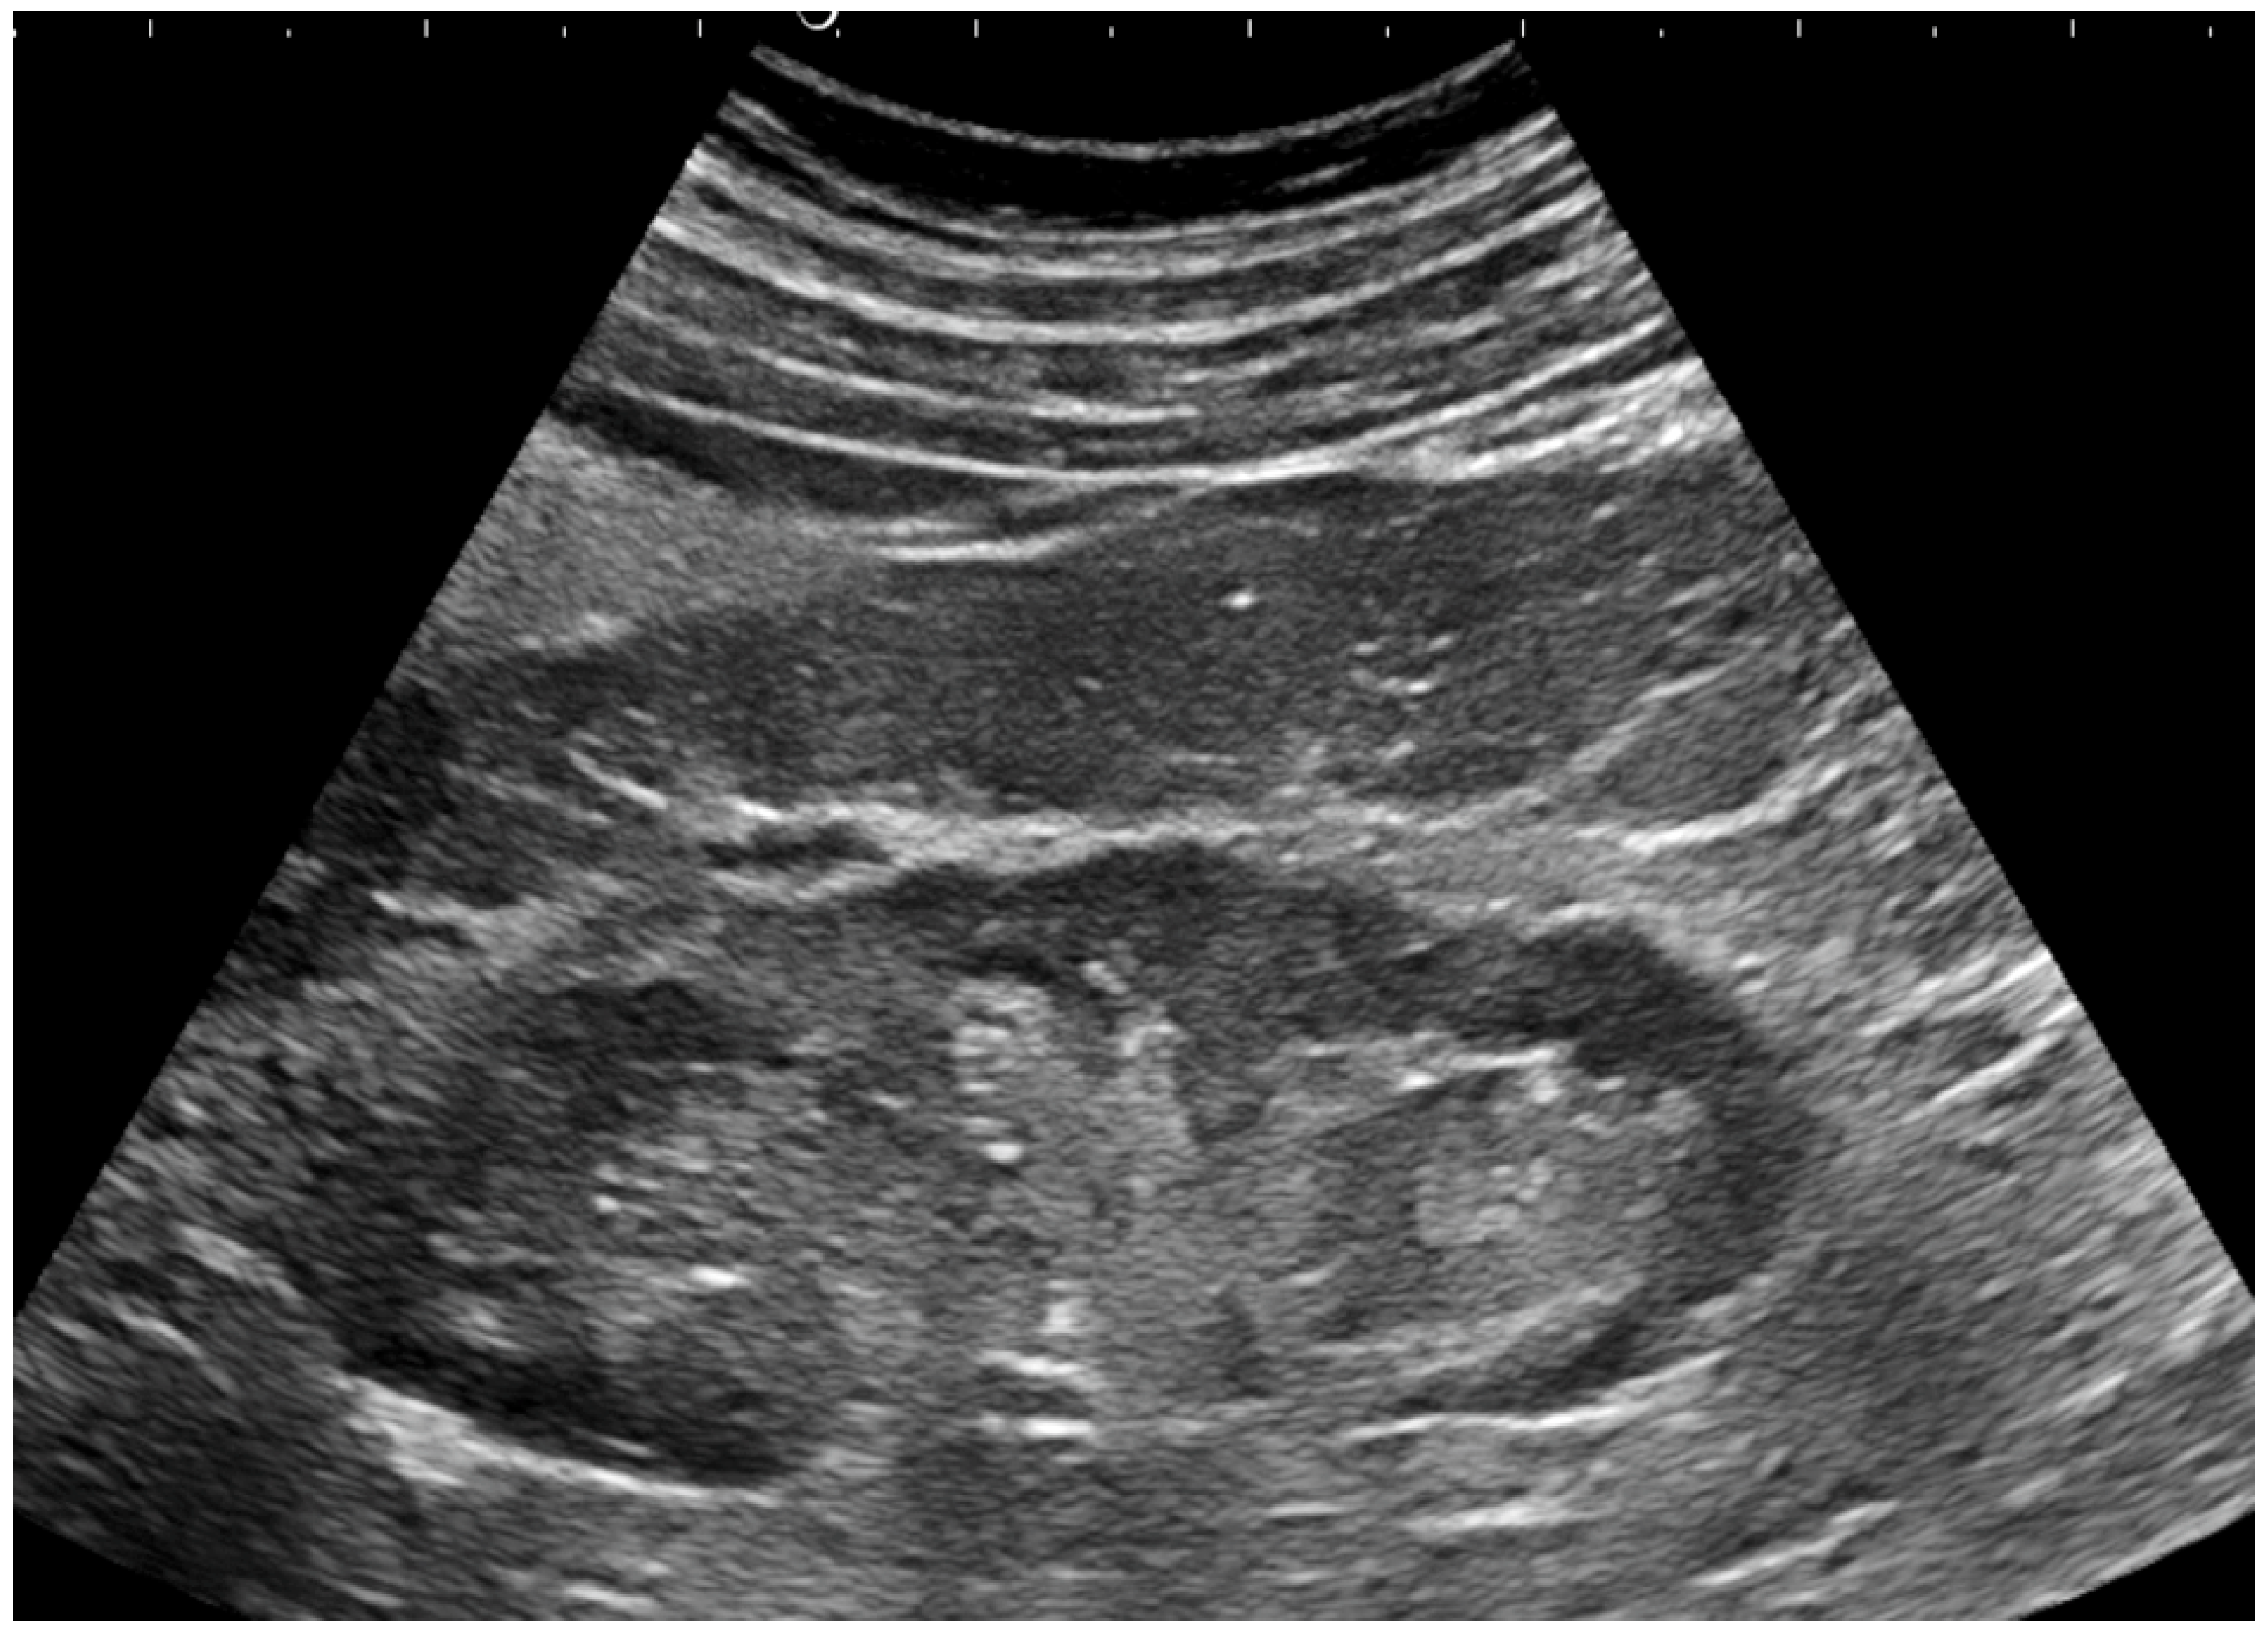

- Bardin, T.; Nguyen, Q.D.; Tran, K.M.; Le, N.H.; Do, M.D.; Richette, P.; Letavernier, E.; Correas, J.-M.; Resche-Rigon, M. A cross- sectional study of 502 patients found a diffuse hyperechoic kidney medulla pattern in patients with sereve gout. Kidney Int. 2021, 99, 218–226. [Google Scholar] [CrossRef]

- Bardin, T.; Tran, K.M.; Nguyen, Q.D.; Sarfati, M.; Richette, P.; Vo, N.T.; Bousson, V.; Correas, J.-M. Renal medulla in severe gout: Typical findings on ultrasonography and dual-energy CT study in two patients. Ann. Rheum. Dis. 2018, 78, 433–434. [Google Scholar] [CrossRef]